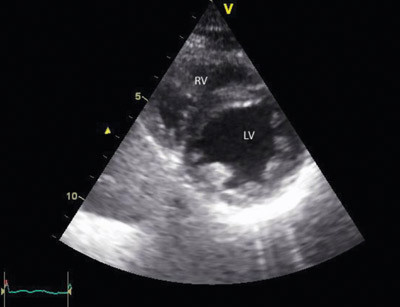

Ved overflytting til lokalsykehuset viste ekkokardiografi normale dimensjoner på alle kamre, god kontraktilitet av venstre ventrikkel (fig 4), noe paradoks bevegelse av septum, ingen trikuspidalinsuffisiens, lett redusert funksjon av høyre ventrikkel bedømt ut fra vevsdopplerundersøkelse av trikuspidalannulus (grenseverdier).